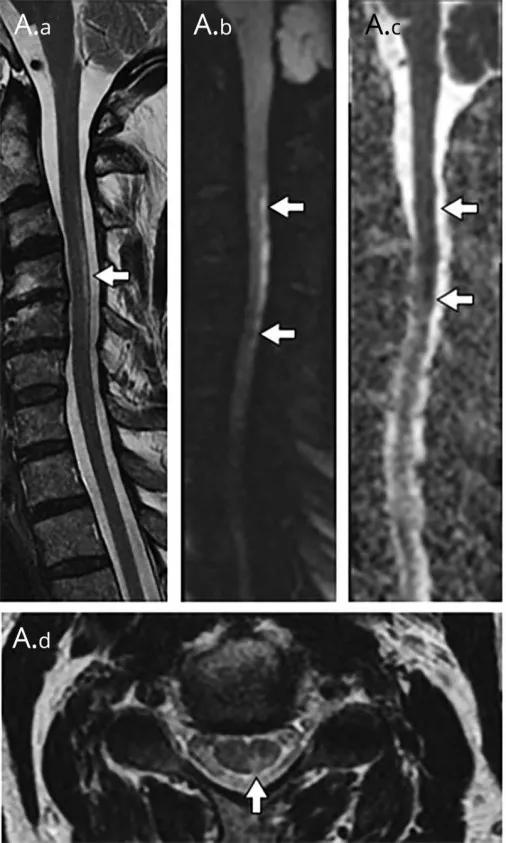

脊髓梗死(spinal infarction),各种原因(比如动脉夹层、椎体术后、纤维软骨栓塞等等)导致的脊髓供血动脉缺血,脊髓前动脉最多见

MRI:

前 2/3 脊髓(脊髓前动脉);双侧灰质前角(脊髓前动脉);后索(脊髓后动脉)

T2WI 高信号病灶,DWI 呈高信号,ADC 呈低信号

轴位「鹰眼征」

矢状位「铅笔征」

脊髓前动脉梗死导致双侧灰质前角梗死(鹰眼征),矢状位呈线样,DWI 提示细胞毒性水肿

脊髓前动脉梗死导致脊髓前 2/3 梗死,DWI 提示细胞毒性水肿

脊髓后动脉梗死导致脊髓后索梗死,DWI 提示细胞毒性水肿

Sulcal 动脉梗死

硬脊膜动静脉瘘 (spinal dural arteriovenous fistula,SDAVF):供应脊膜或神经根的细小动脉,在椎间孔处穿过硬膜与脊髓引流静脉相通,导致脊髓回流受阻。病因不明,成人-老年人胸腰段多见,缓慢起病,进行性加重。

矢状位 T2WI 发现长节段高信号

矢状位 T2WI 脊髓周围流空低信号血管影

部分可见强化,提示血脑屏障破坏

脊髓内长节段T2WI高信号,髓周可见多发点状流空血管,增强扫描出现强化